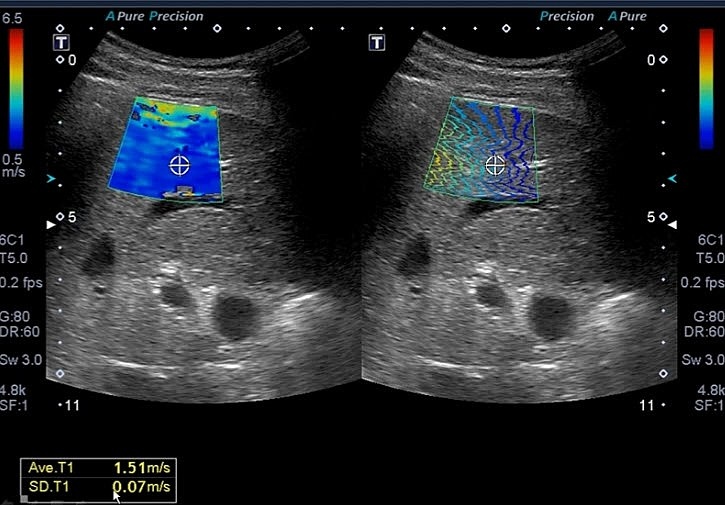

УЗИ стеатометрия печени

2. Диагностика:

· ультразвуковой датчик передвигается по области правого подреберья;

· проводится оценка эхогенности ткани печени, её структуры и наличия жировых отложений.

3. Результаты:

На основе эхографической плотности определяется степень стеатоза:

• 0 — норма (жировых включений нет);

• 1 — лёгкая степень (жировые отложения до 33%);

• 2 — умеренная степень (жировые отложения до 66%);

• 3 — тяжёлая степень (жировые отложения более 66%).